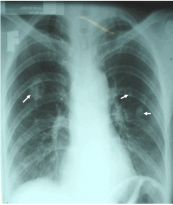

Hạch trung thất to và đối xứng trong Sarcoidose trên phim chụp x quang ngực. Mời các bạn tham khảo một số thông tin dưới đây để hiểu rõ hơn nhé!